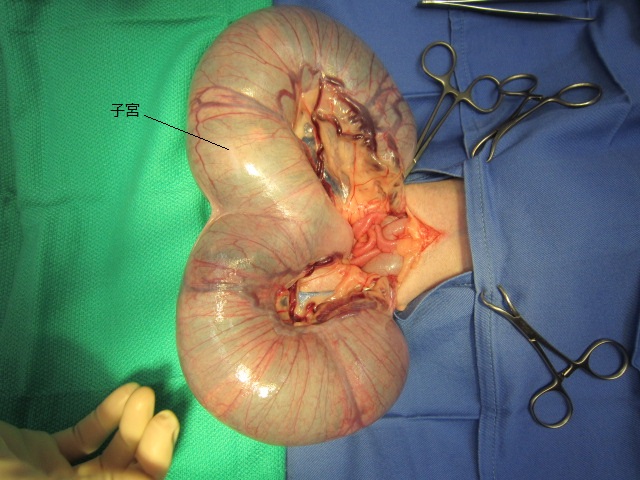

術中の様子です。

肥大した子宮を出した所です。

子宮を切って胎子を取り出します。